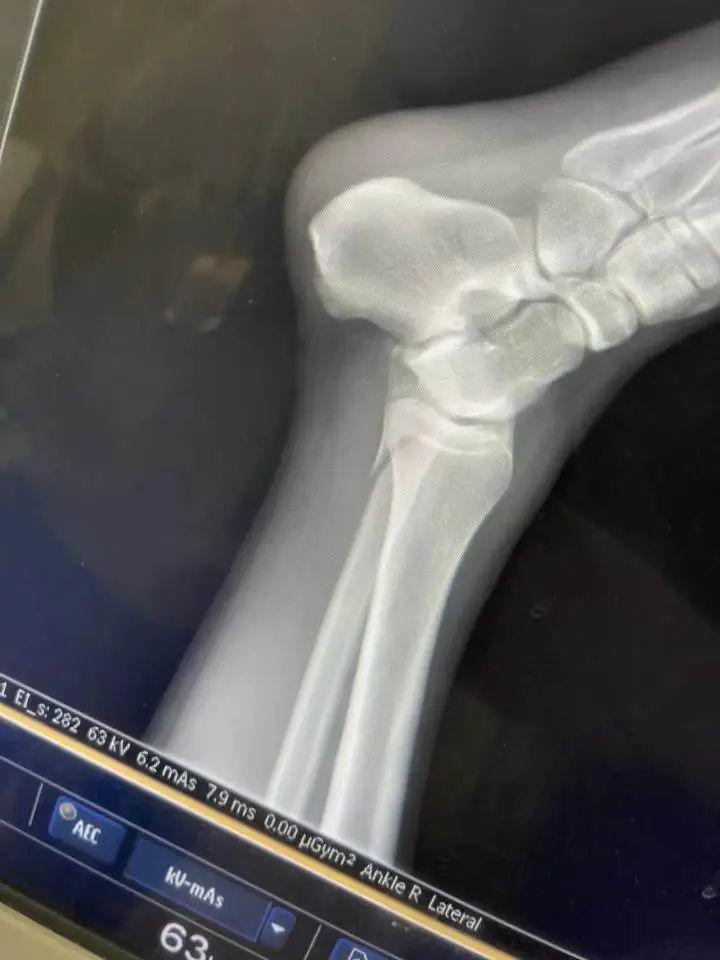

“我感觉是水比较浅,水下有个不平的东西,当时一瞬间还没感觉,脚崴了,只好硬撑着走,走上岸就走不动了,脚已经使不上劲儿了。最后用一只脚蹦到救护车上。”

“我就把躺的位置让给她,她的腿骨折了,我是踝骨受伤。现场的工作人员让我们到二级以上的公立医院治疗,然后报销。”

“医院建议我动手术,我当时打算,先保守治疗吧,因为自己还年轻,不能因为这点事儿动刀。”

小黄说,自己落水受伤后,腿已经肿起来,动不了。自己花钱雇救护车回到了无锡,昨晚没睡着,好疼。